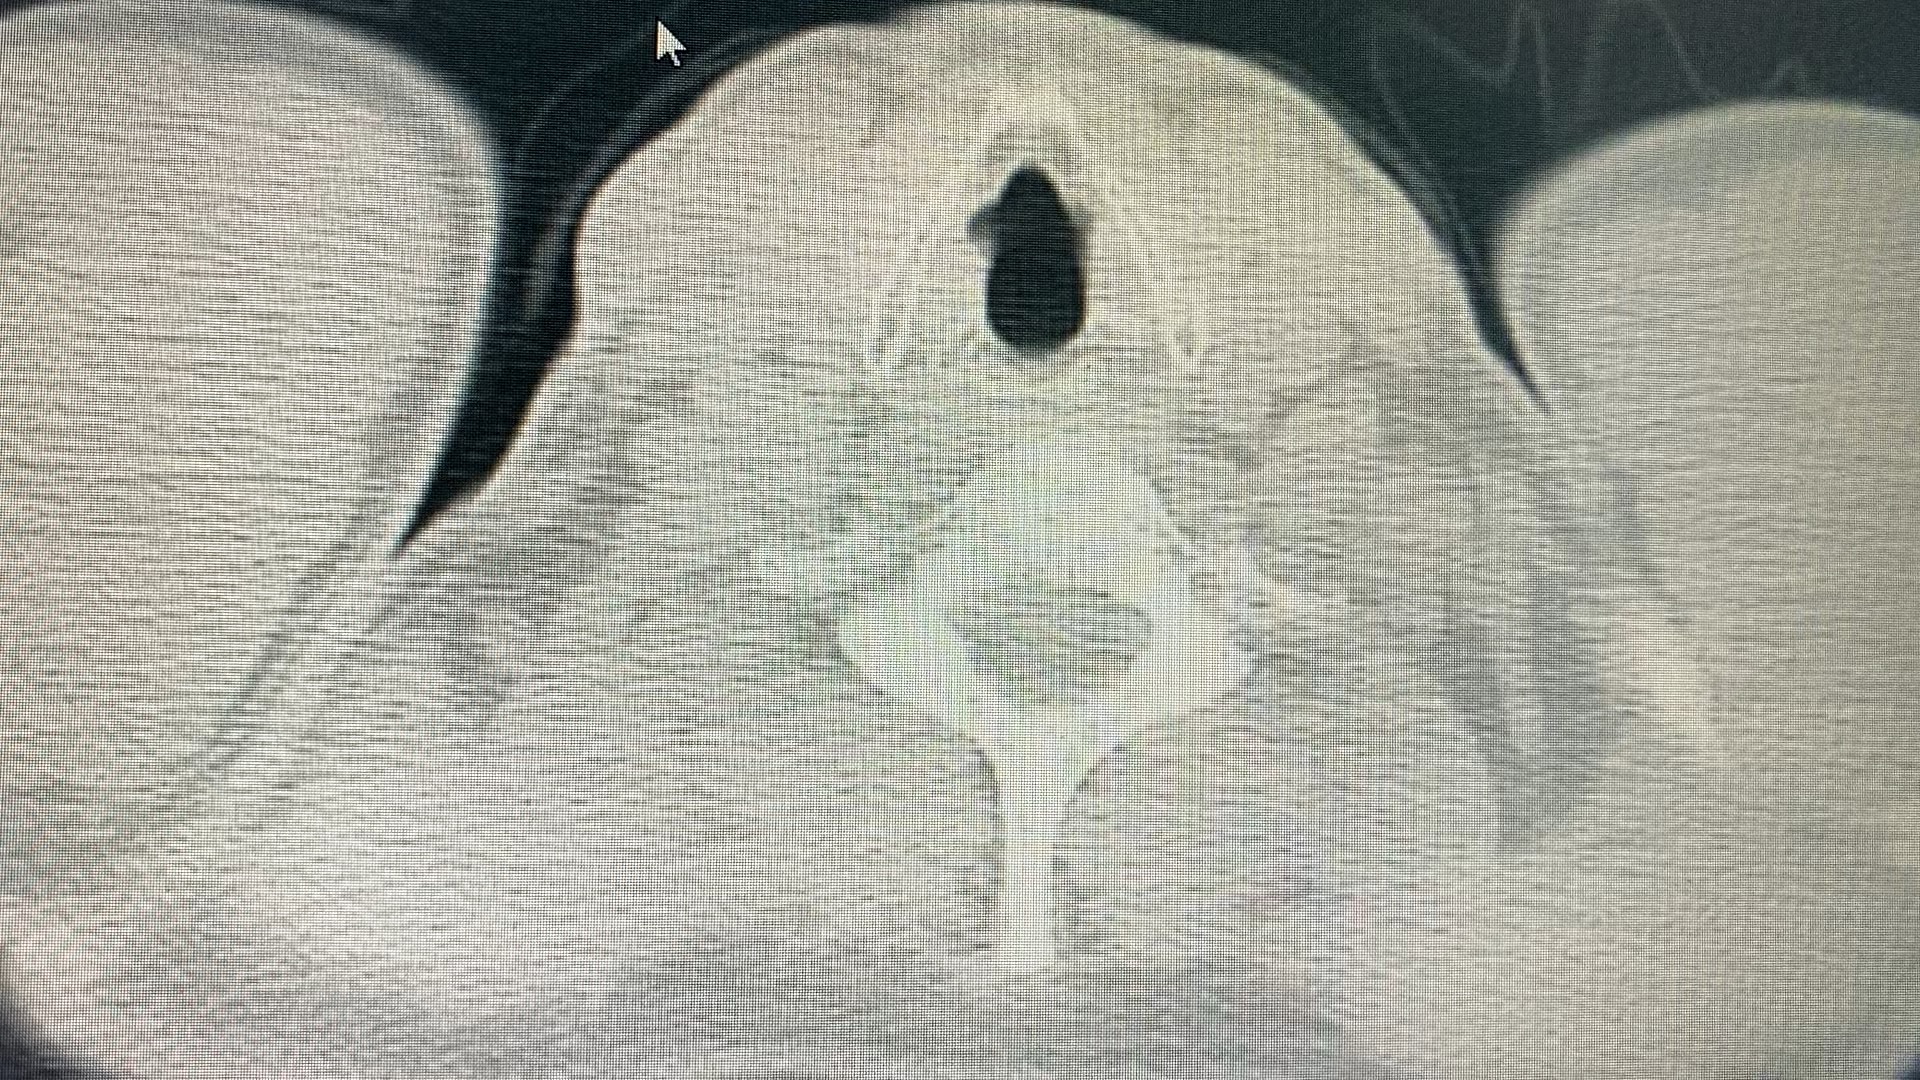

患者男,55岁,发现肺部结节6年。无特殊不适。既往无特殊病史。

2025.10.30